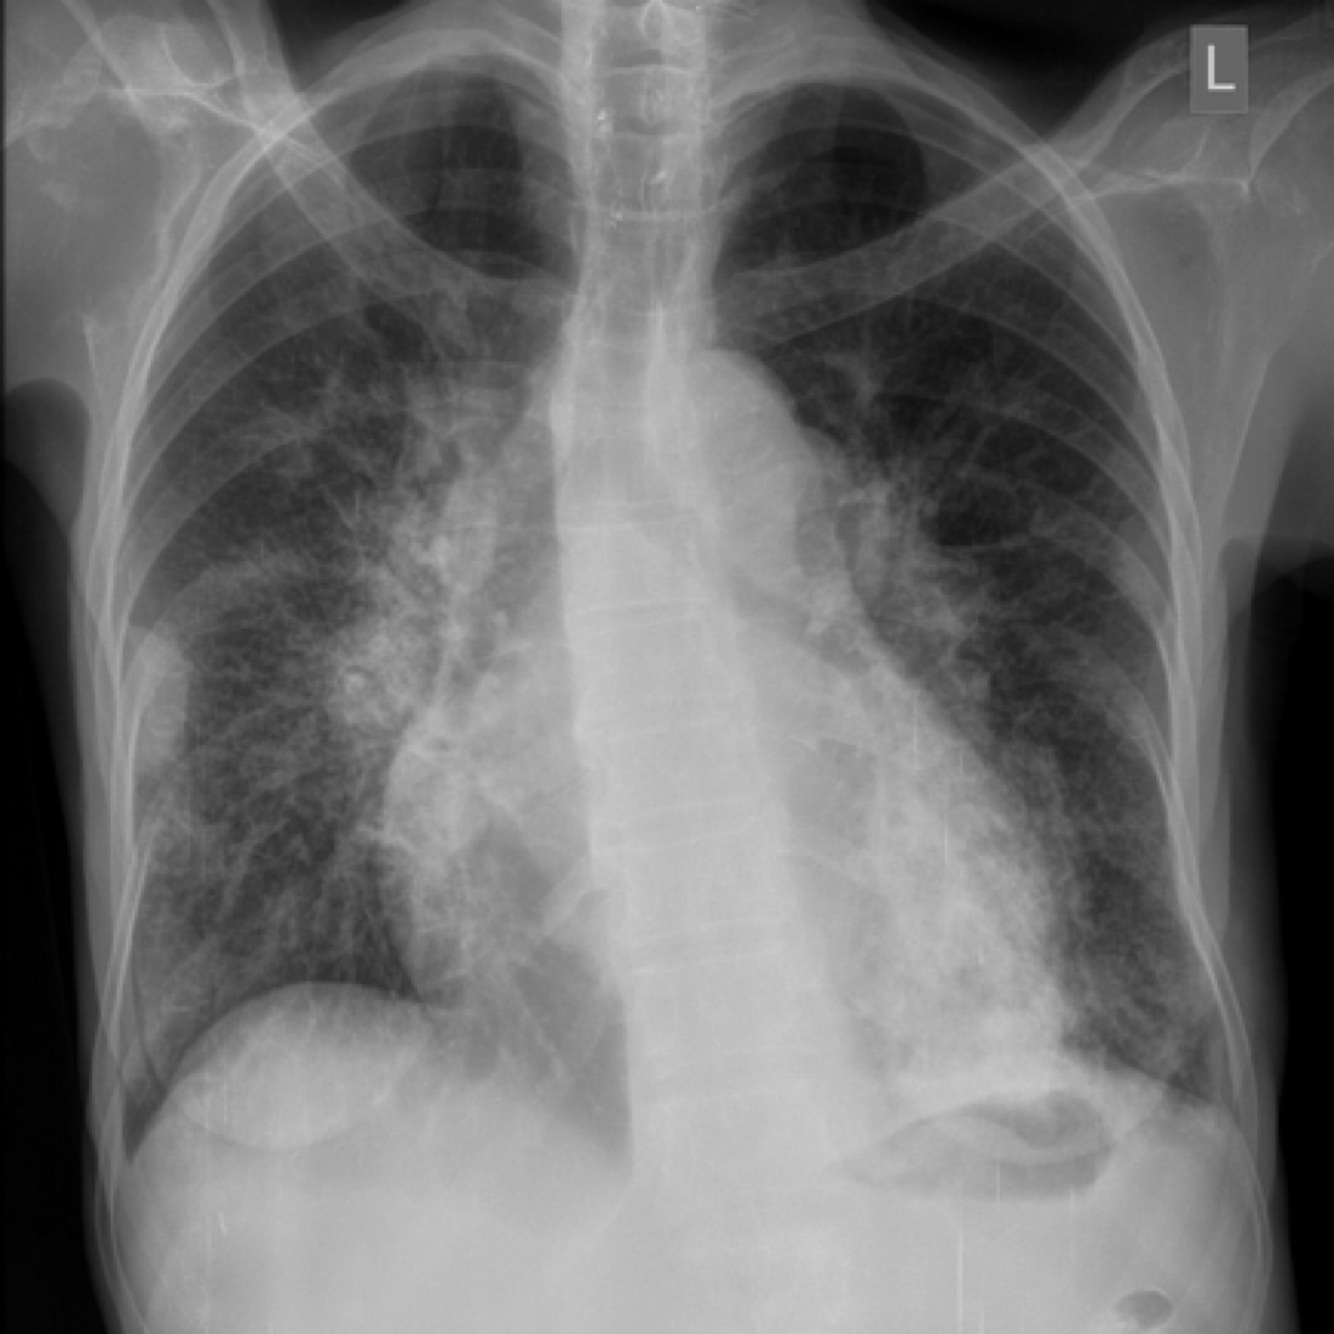

Which resp disease is this?

Reticulo-nodular shadowing as in interstitial lung disease